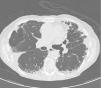

Chest X-rays showed intense apical pleural thickening and upper hilar retraction. The chest CT revealed bilateral irregular pleuroparenchymal thickening, principally in the upper and middle areas, associated with fibrotic signs (Fig. 1). Serology tests were negative for anti-scl-70, anti-Jo-1 and anti-DNA antinuclear antibodies, antineutrophil cytoplasmic antibodies, rapid plasma reagin and rheumatoid factor. A videobronchoscopy with bronchoalveolar lavage was carried out and transbronchial biopsies were obtained, giving negative cytology and microbiology results. Histopathology examination of the lung biopsy showed intraalveolar fibrosis without granulomas. The complementary imaging studies and examinations were compatible with IPPFE and the patient was initially treated with low-dose oral azathioprine and corticosteroids. After 24h, the patient showed disease progression with no response to treatment, requiring home oxygen therapy. A recent chest CT showed loss of volume and progression of pleural thickening, along with signs of fibrosis in the lower lobes. Follow-up lung function tests showed FVC 58% and FEV1 67%.